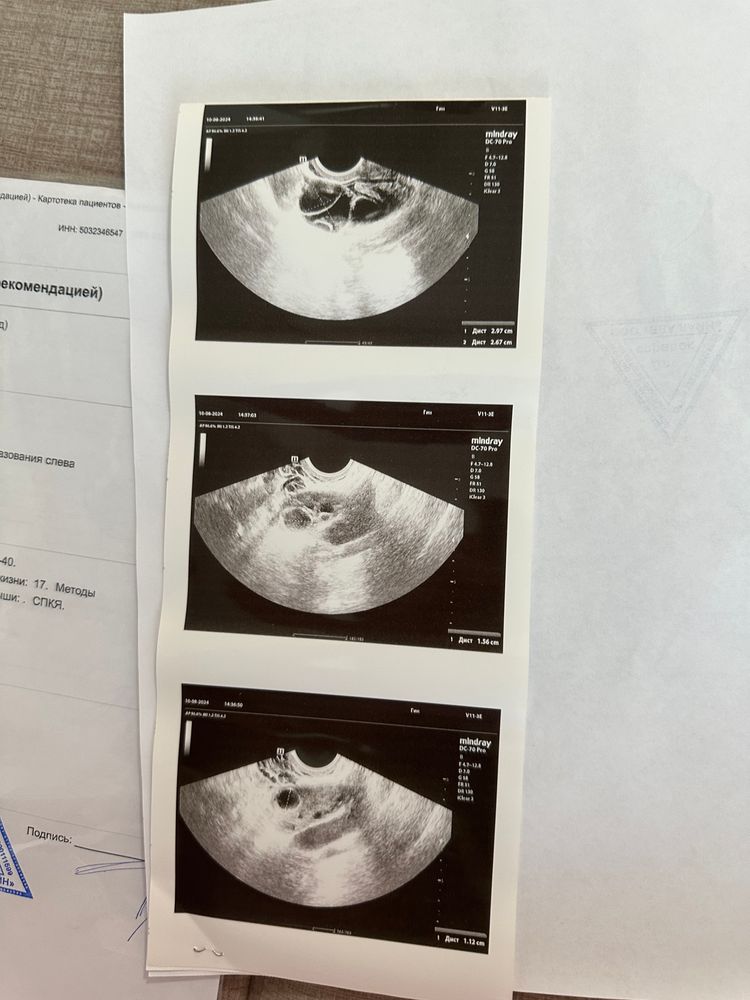

Девочки, страшно до ужаса, сегодня на узи обнаружили ещё и 2 кисту. Они обе по 3см примерно. Назначили анализы на онкомаркеры…Боже как мне страшно, я сойду с ума. На сколько опасны эти кисты? Говорят что их можно перепутать с цестоденомой…а это же вообще рак 😭😭😭

Ася, я пере проверила диагноз в 2 клиниках. Это точно паровариальные кисты…Меня пугают анализы на онкомаркеры